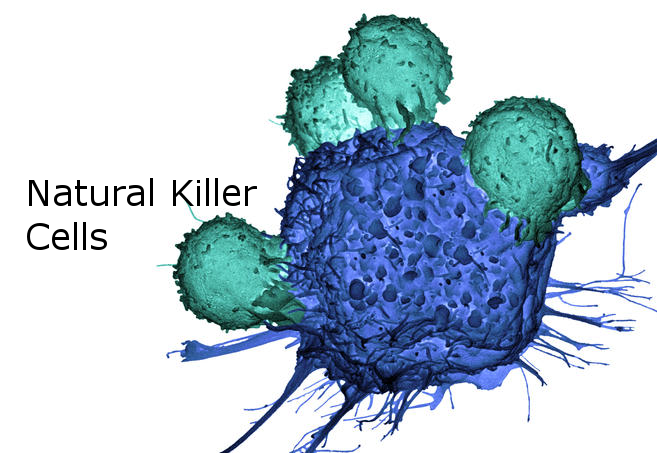

Иллюстрации из Cell Discovery: Удивительный мир науки через фотографии

Раздел: Фотоэссе